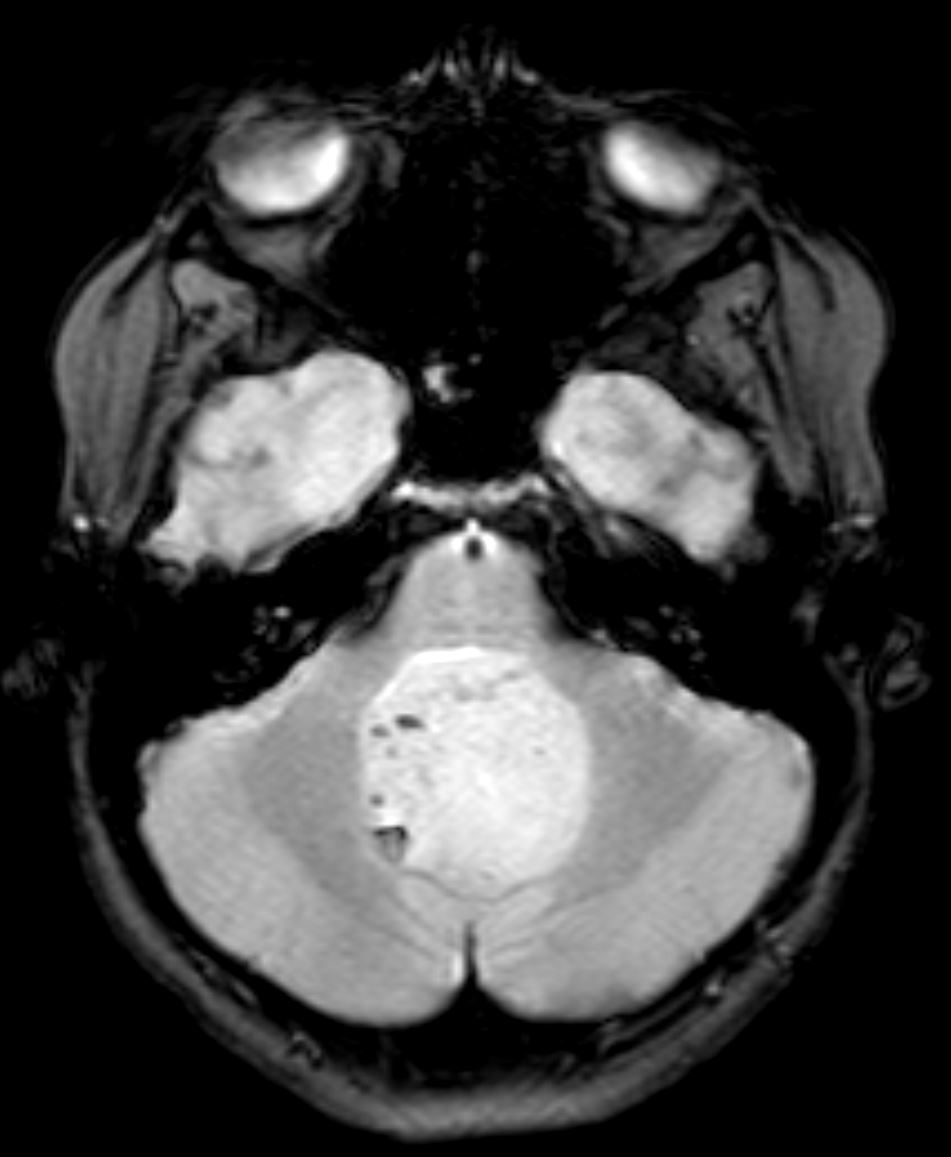

Image IQ Quiz: Pediatric Patient Presents with Double Vision

Pediatric patient presents with double vision. What is the most likely diagnosis?